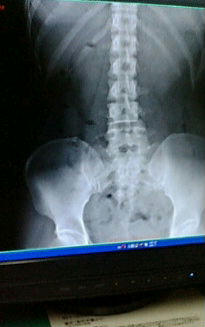

画像は本日撮った私の腰骨のレントゲン。

これを置いたまま10分くらい待たされてたので、こっそり写メ(^_^;)

わかりにくいけど筋肉のラインもうっすら見えてて、

そこから皮膚のラインまでの厚みって・・・つまり皮下脂肪ですかね。

なんだこの分厚さ。

ちなみに腰ホネに異常なし♪

・・・・・年相応だってさ(>_<)